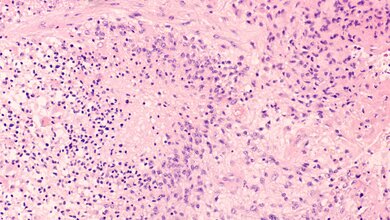

Die Diagnose Glioblastom gleicht noch immer einem Todesurteil. Die mittlere Überlebenszeit beträgt unverändert nur etwa 14 bis 15 Monate ab Diagnosestellung. Glioblastome sind die häufigsten und aggressivsten bösartigen Gehirntumore. Durch die operative Entfernung des Tumors und die zusätzliche Strahlen- und Chemotherapie lässt sich meist keine vollständige Heilung erreichen. Der Bedarf nach besseren Behandlungsmöglichkeiten ist entsprechend hoch. Eine neue Kombination aus einem Antikörper, der Krebszellen gezielt entdeckt, und einem Radionuklid weckt bei Reinhard Zeidler, Wissenschaftler bei Helmholtz Munich und am LMU Klinikum, Hoffnung: „Wir glauben, dass wir mit diesem Antikörper Glioblastome besser therapieren und die Lebenserwartung von Betroffenen verlängern können“.

ITM Isotope Technologies Munich SE (ITM), ein radiopharmazeutisches Biotech-Unternehmen, Helmholtz München und die Kliniken für Neurochirurgie und Nuklearmedizin des Universitätsklinikums Münster gaben den Start einer klinischen Phase-I-Studie mit dem Arzneimittelkandidaten ITM-31 (ehemals LuCaFab) von ITM, einem neuartigen Kandidaten für die gezielte Radionuklidtherapie zur Behandlung von malignem Glioblastom bekannt. ITM-31 ist ein Carboanhydrase (CA) XII-spezifisches Antikörper-Fab-Fragment, das von Helmholtz München entwickelt wurde und mit dem medizinischen Radioisotop Lutetium-177 (n.c.a 177Lu, EndolucinBeta®) von ITM gekoppelt ist. Die Studie wird vom Universitätsklinikum Münster gefördert, an Kliniken in Münster, Essen, Köln, Würzburg durchgeführt und von ITM und Helmholtz München unterstützt. Die Patientenrekrutierung für die Studie läuft.